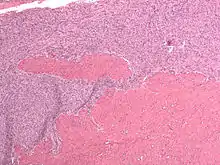

Endometrial stromal sarcoma (low-grade)

Microscopy

- Monotonous ovoid cells to spindly cells with minimal cytoplasm.

- Prominent arterioles. Angiolymphatic invasion common.

- Up to 10-15 mitotic figures per 10 HPF in most active areas.

- Tongue-like infiltration between muscle bundles of myometrium.

- May exhibit myxoid, epithelioid and fibrous change.

- May have foam cells or hyalinization in the stroma.